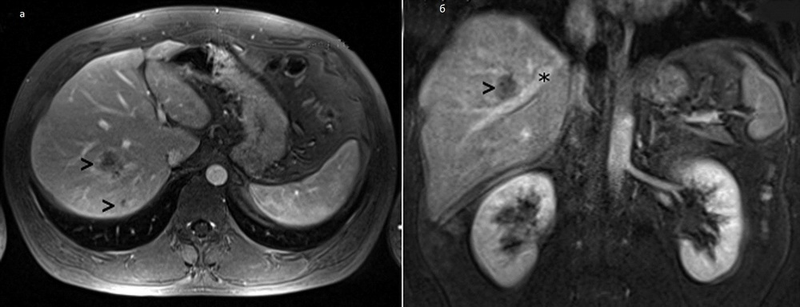

Методы динамического контрастирования печени на МРТ

Раздел: Снимки-подсказки